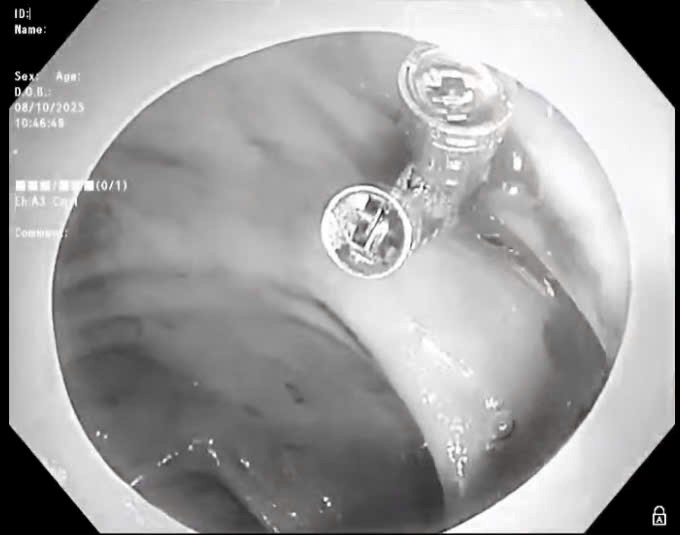

BVĐK Sóc Sơn cấp cứu thành công ca bệnh sốc giảm thể tích do xuất huyết tiêu hóa

Thứ Sáu, ngày 17/10/2025 05:02Vừa qua, Bệnh viện đa khoa (BVĐK) Sóc Sơn đã tiếp nhận bệnh nhân Đỗ Văn P (69 tuổi) ở Sóc Sơn, được người nhà đưa đến bệnh viện cấp cứu. Các bác sĩ xử trí kịp thời ca bệnh sốc...